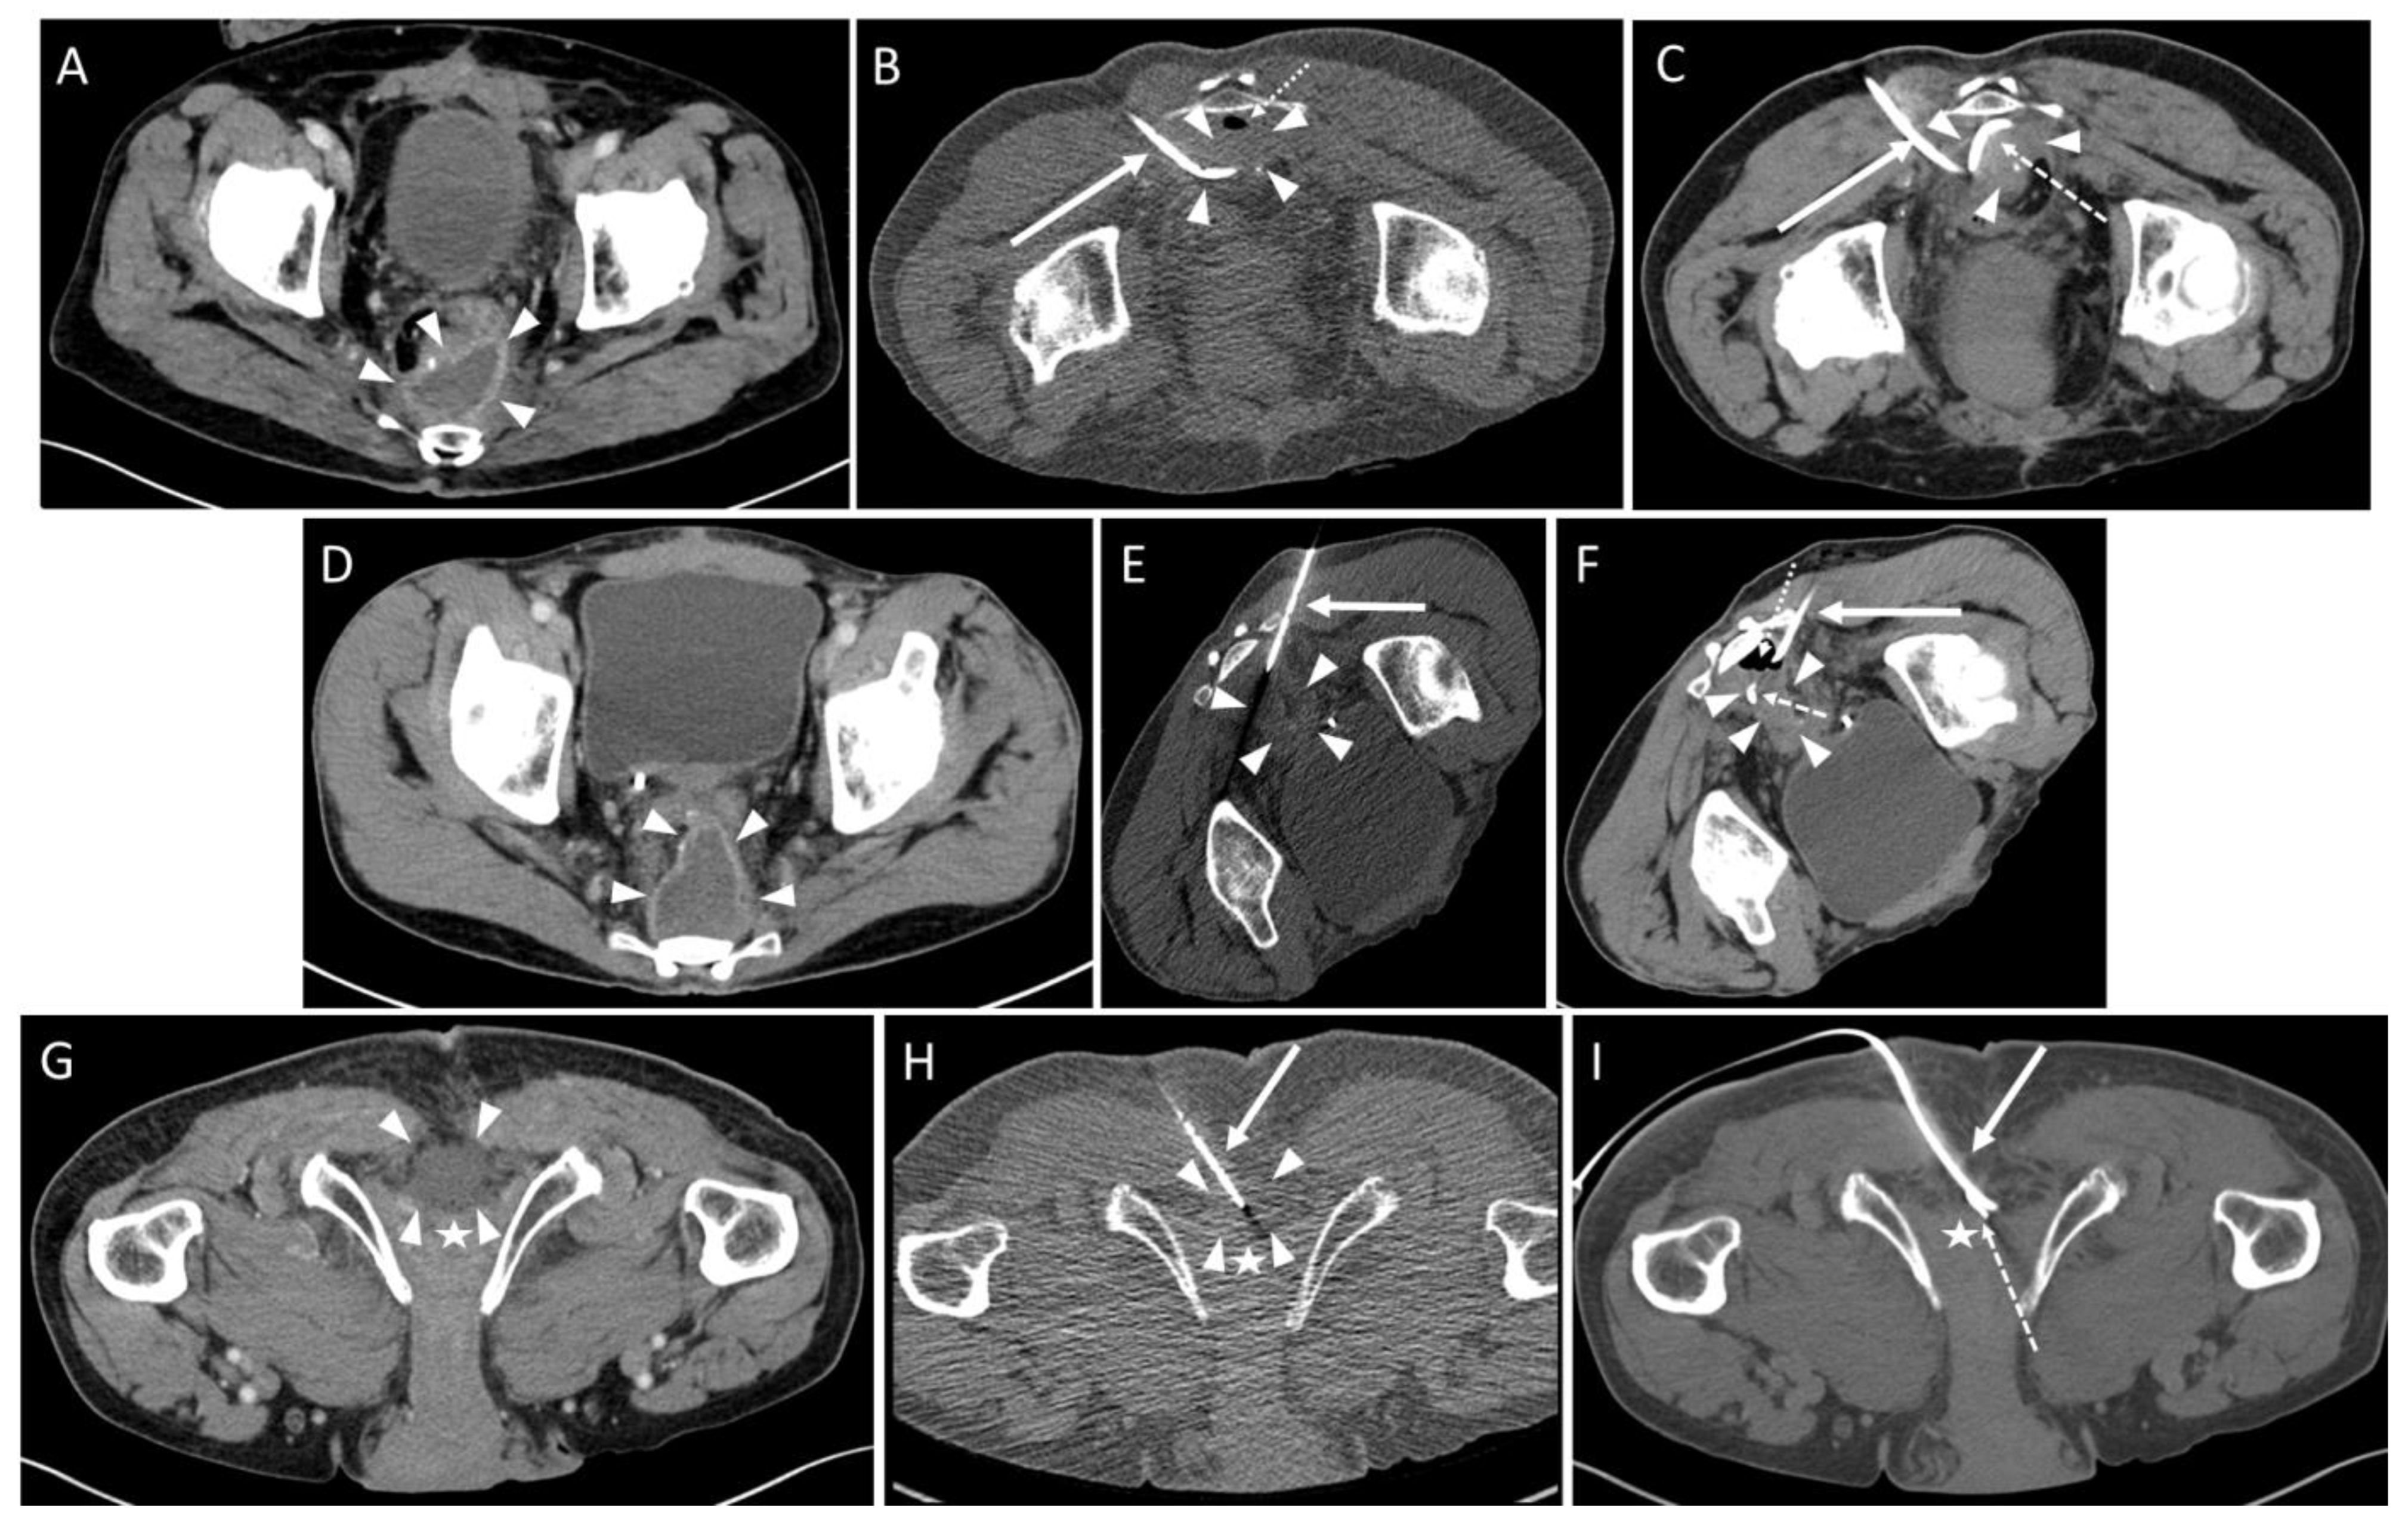

3.2. Pre- and Peri-Interventional Analysis

| Technique | Count |

| Trocar | 40 (93.0%) 3 |

| Seldinger | 3 (7.0%) 3 |

| Approach | |

| parasacral | 29 (72.5%) 3 |

| paracoccygeal | 10 (25.0%) 3 |

| infracoccygeal | 1 (2.5%) 3 |

| Access path | Count |

| transpiriform | 8 (20.0%) 3 |

| infrapiriform | 31 (77.5%) 3 |

| transperineal | 1 (2.5%) 3 |